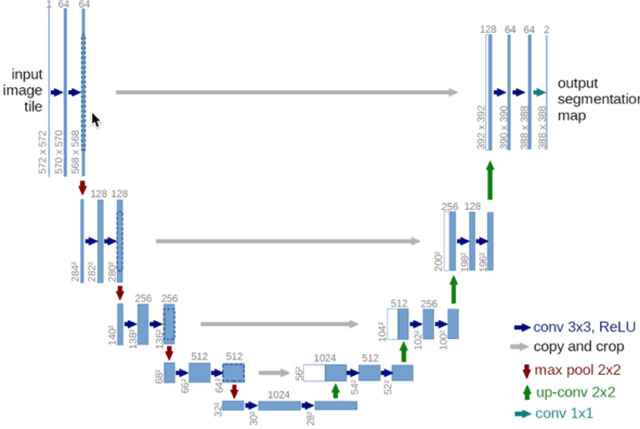

Detection and Classification of Breast Cancer Metastates Based on U-Net

Sep 09, 2019

This paper presents U-net based breast cancer metastases detection and classification in lymph nodes, as well as patient-level classification based on metastases detection. The whole pipeline can be divided into five steps: preprocessing and data argumentation, patch-based segmentation, post processing, slide-level classification, and patient-level classification. In order to reduce overfitting and speedup convergence, we applied batch normalization and dropout into U-Net. The final Kappa score reaches 0.902 on training data.